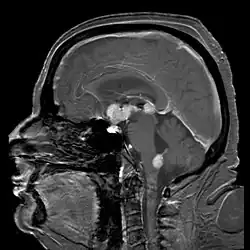

Brain magnetic resonance imaging showing primary central nervous system B-cell non-Hodgkin lymphoma of the sella turcica and hypothalamus, continuing to the tectum (intensely white areas in the middle).

MRI or contrast enhanced CT classically shows multiple ring-enhancing lesions in the deep white matter. The major differential diagnosis (based on imaging) is cerebral toxoplasmosis, which is also prevalent in AIDS patients and also presents with a ring-enhanced lesion, although toxoplasmosis generally presents with more lesions and the contrast enhancement is typically more pronounced. Imaging techniques cannot distinguish the two conditions with certainty, and cannot exclude other diagnoses. Thus, patients undergo a brain biopsy or vitreous biopsy, if there is intraocular involvement.[10] Another diagnostic challenge is distinguishing PCNSLs from high-grade gliomas. On MRI, PCNSLs typically show a more homogenous contrast enhancement whereas high-grade gliomas have a more heterogeneous contrast enhancement with necrotic area. However, a brain biopsy can be needed to distinguish between these two brain tumours. [12]